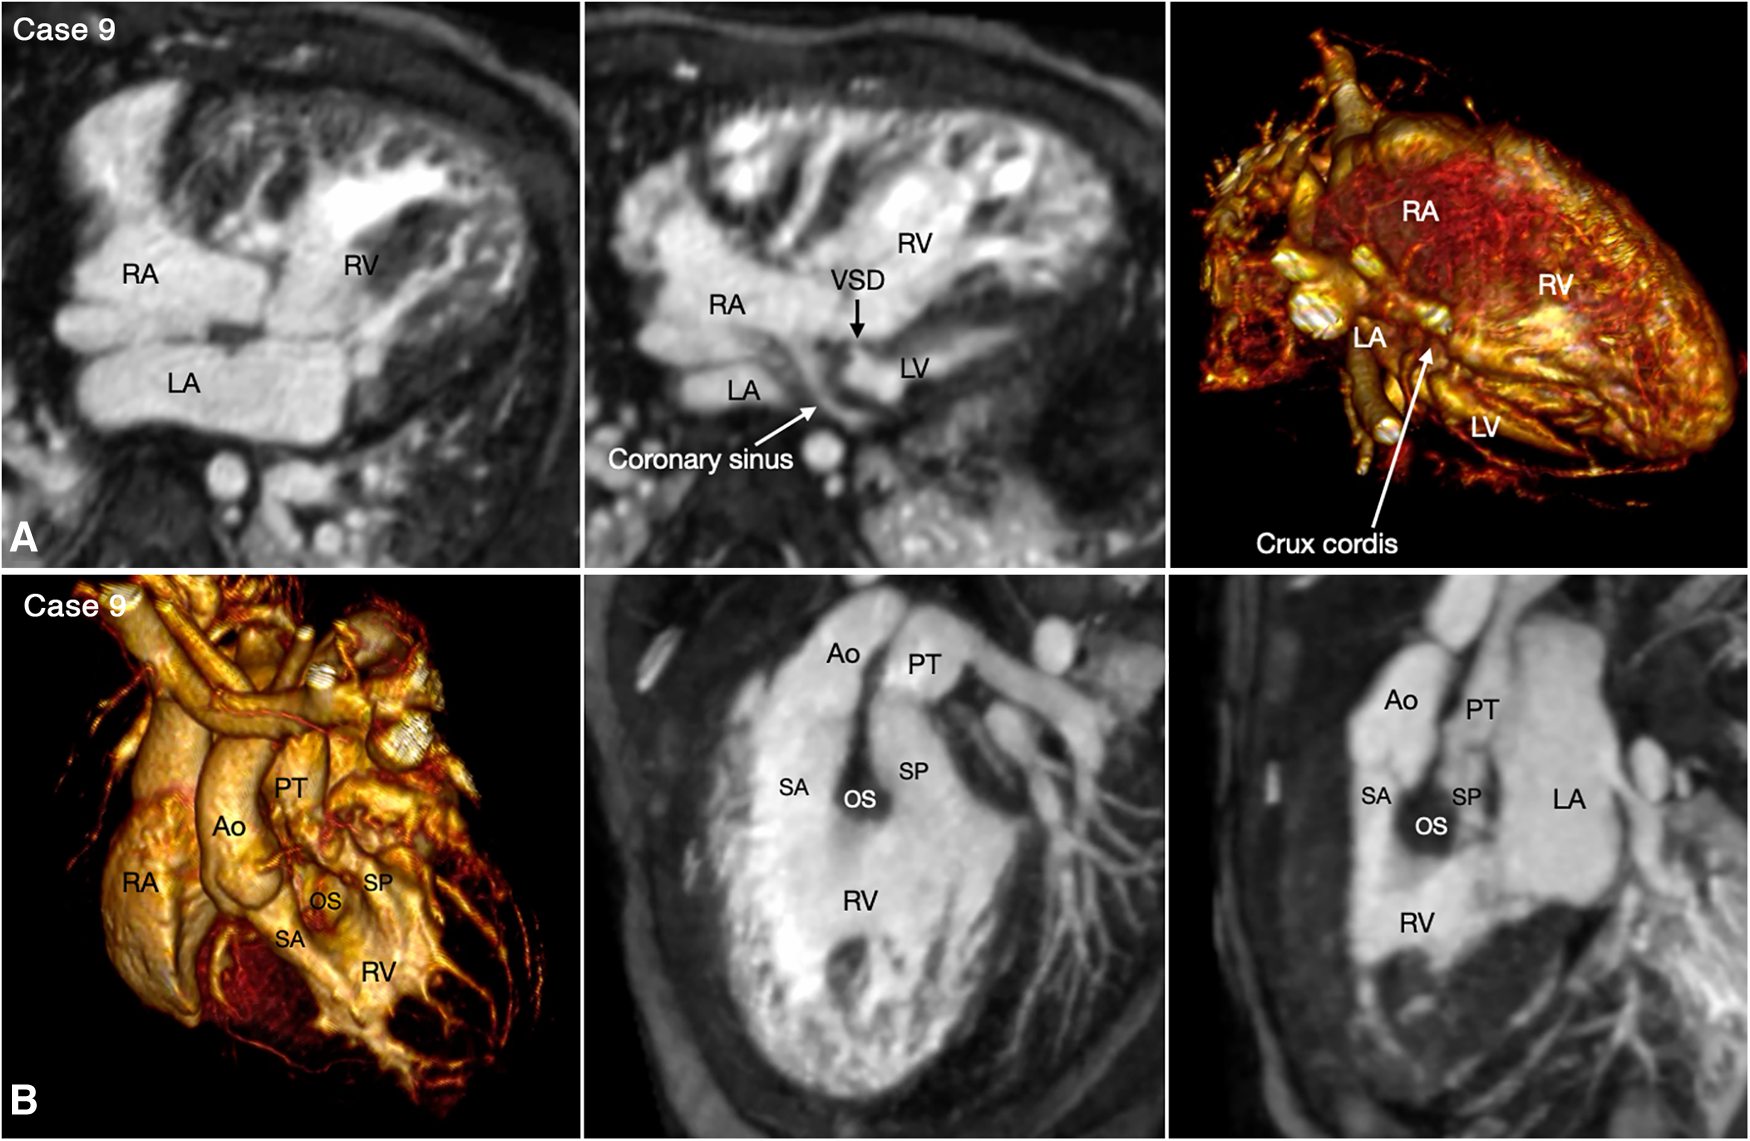

Figure 9

(Case 9). Double inlet and double outlet right ventricle in a patient with situs solitus and levocardia. (A) Maximum intensity projection images (MIP) in 4-chamber planes (left and middle panels) and volume rendered (VR) image (right panel) seen from below simulating the view in the middle panel. Both right (RA) and left (LA) atria connect to the main chamber of right ventricular morphology (RV). The severely hypoplastic left ventricle (LV) is positioned along the diaphragmatic surface at the left corner of the crux cordis. (B) VR images in left anterosuperior view (left panel) and MIP images in steep left anterior oblique planes (middle and right panel). The VR image and MIP image in right panel were obtained in end systole and the MIP image in the middle panel was obtained in end diastole. Both aorta (Ao) and pulmonary arterial trunk (PT) arise from the right ventricle. The right ventricular outflow tract is divided into the subaortic (SA) and subpulmonary ((SP) outflow tracts by the hypertrophied outlet septum (OS). Both outflow tracts show severe dynamic narrowing in systole. The aorta is positioned on the right anterior aspect of the pulmonary arterial trunk.